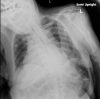

Rare Presentation of Cardiac Tamponade in a Patient With Subclinical Hypothyroidism

Cardiovascular effects of hypothyroidism include bradycardia, diastolic hypertension, atrial fibrillation, prolonged QT interval leading to torsades de pointes, varying degrees of AV block, accelerated coronary artery disease, and pericardial effusion. Cardiac tamponade is rare in patients with hypothyroidism because of pericardial distensibility and slow accumulation of fluid. The amount and rate of accumulation of pericardial effusion are related to the severity of hypothyroidism. Though rare, significant pericardial effusion can be a manifestation of subclinical hypothyroidism.